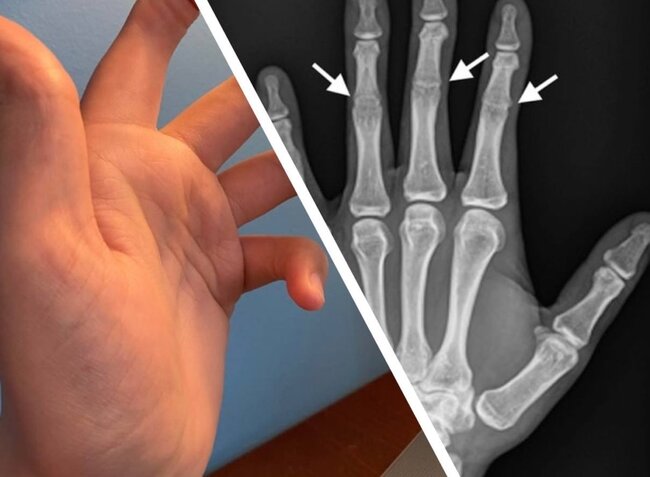

Bu adamın əlində orta oynaqlar YOXDUR - FOTO

Bu adamın əlində orta oynaqlar YOXDUR - FOTOBarmaqlarınızda orta oynaqlar olmadan özünüzü təsəvvür edə bilərsiniz? Həyatınızın nə dərəcədə çətinləşəcəyini anlatmağa ehtiyac yoxdur. Barmaqlar bükülmədən heç yazı yazmaq belə, mümkün deyil.

Bu adamın əlində orta oynaqlar YOXDUR - FOTOQeyd edək ki, sümük inkişafına təsir edən bu nadir irsi xəstəlik simfalangizm adlanır.